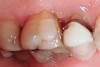

Figure 4   Indentations on tongue caused by forceful pressing of tongue on lingual surfaces. By pushing the tongue anteriorly, the airway is opened.

Figure 4